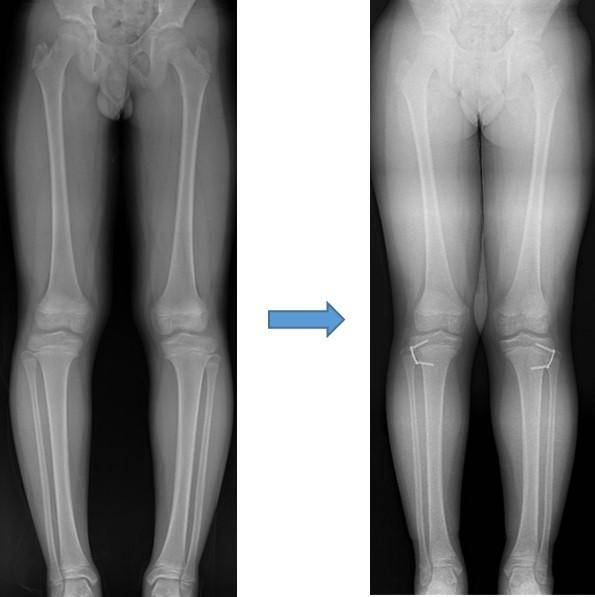

# 수진(가명·여·10세)양의 어머니는 아이의 다리가 살짝 휘어 보여 걱정이었다. 양쪽 무릎이 아프다며 한동안 밤잠도 설치는 아이를 보니 걱정은 더욱 커졌다. 결국 아이와 함께 병원을 찾았다. 엑스레이 검사 결과 X자형으로 다리가 휜 외반슬을 진단받았고, 교정을 위해 반성장판 유합술을 받았다. 수술 후 1년이 지난 지금 수진 양의 다리 변형은 완전히 교정됐고 무릎 통증도 사라졌다.

수술 방법으로는 ‘교정 절골술’이나 ‘반성장판 유합술’이 있는데, 이 중 반성장판 유합술은 일시적으로 한쪽 성장판의 기능을 억제해 아이가 성장하면서 변형이 교정될 수 있도록 하는 수술법입니다.

최근에는 ‘8’자 모양의 금속판을 이용한 ‘반성장판 유합술’이 시행되고 있습니다. 이 방법은 교정이 완료돼 금속판을 제거하면 성장이 재개되기 때문에 상대적으로 더 어린 나이에 시행이 가능합니다.

수술시기를 비교적 편하게 잡을 수 있고, 효과적인 교정을 얻을 수 있다는 것이 장점입니다. 또한 입원기간이 평균 하루 정도로 짧고 회복이 빨라 대부분의 경우 바로 활동이 가능합니다.